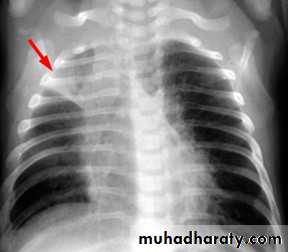

Unilateral obstructive emphysemaunilateral emphysema or atelectasis are the most common findings; only uncommonly will a radio-opaque foreign body be demonstrated ,Aspirated foreign bodies have a predominance for the right tracheo bronchial tree.